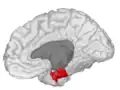

Additional images

Entorhinal cortex, shown in the right cerebral hemisphere.